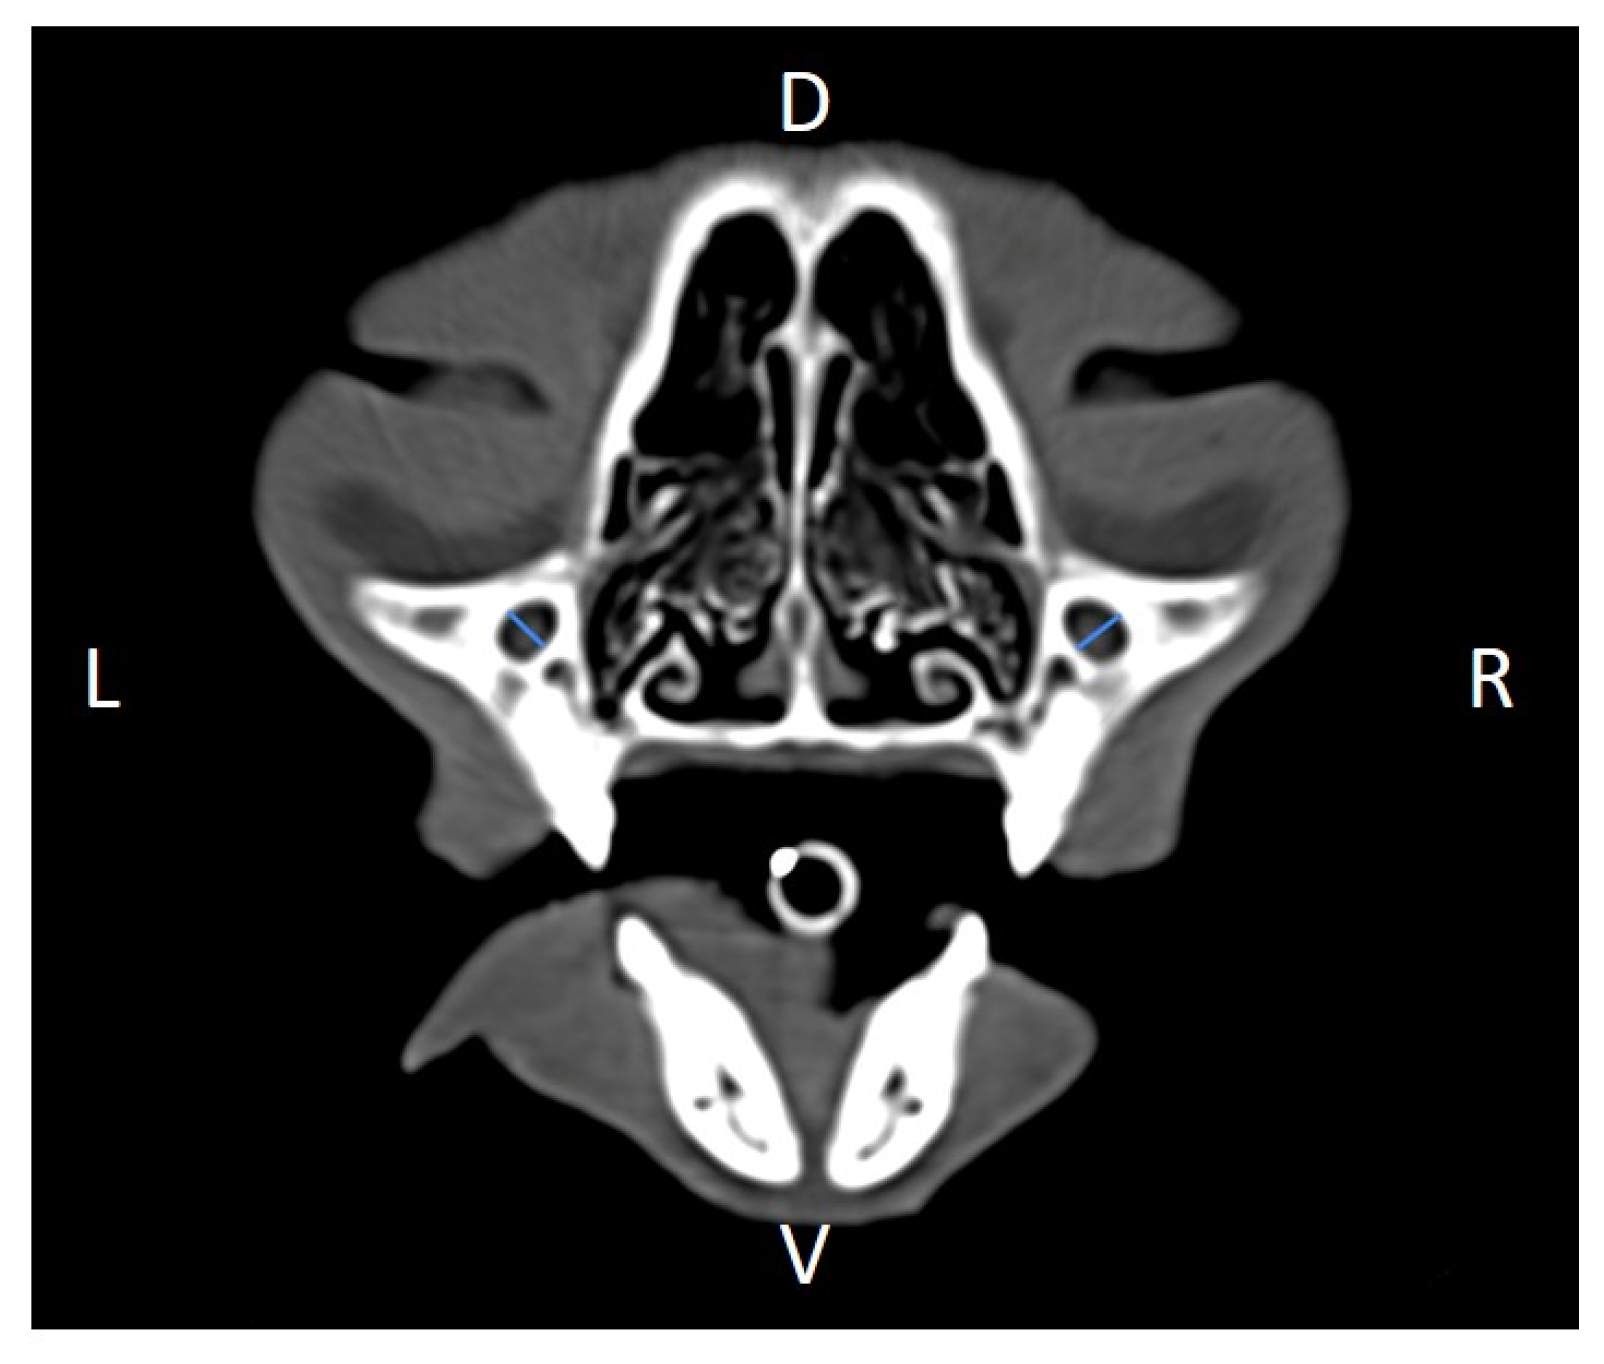

Linear morphometric parameters (Table 1) were obtained directly from CT images using HorosTM v3.3.6.dmg DICOM software with bone filters. Prior to measurement, all images were calibrated from pixels to millimeters. A preliminary study and prior training were conducted, to establish anatomical landmarks that would allow for the repeatability of the measurement methodology by J.F.R., A.R.S., S.A.-P. Recorded variables included infraorbital foramen major axis (Figure 2), minor axis (Figure 3) and length (Figure 4), distance between infraorbital foramina (DIF) (Figure 5), orbital height and width (Figure 6 and Figure 7), zygomatic arch width (Figure 8), skull width and length (Figure 9). Ratios were calculated to normalize for skull size. As preliminary results revealed adequate repeatability of measurements, and in order to reduce the analysis margin of error, two measurements of each studied parameter were performed. The measurements were performed by the same operator (to reduce interpersonal errors), and each measurement of each parameter was performed at different times, in order to reduce intrapersonal errors. Then, the arithmetic mean of the measurements was calculated.

Figure 6. Orbital height (OH) measured at the left and right sides, on a transverse CT image (blue lines). D, dorsal, L, left, R, right, V, ventral.